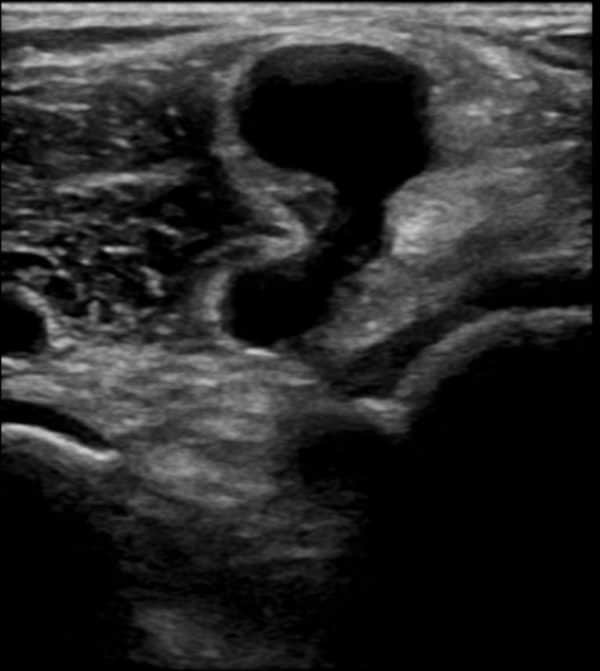

Kén Baker

Kén Baker - Ảnh 2

» Thông tin: Nam giới – 55 tuổi.

» Lâm sàng: Đau vùng khoeo chân.